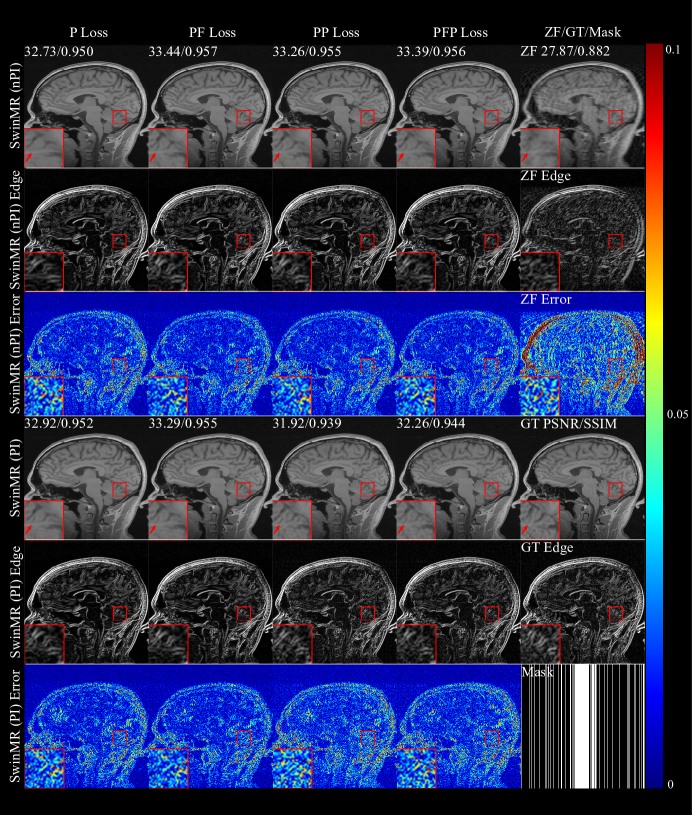

Figure 16 shows the SSIM, PSNR and FID of SwinMR trained with different loss functions. Figure 17 displays the samples of reconstructed images of SwinMR trained with different loss functions.

According to Figure 16, for SwinMR (PI), the utilisation of frequency loss tends to improve SSIM/PSNR and decreases the FID (PFP vs PP; PF vs P). For SwinMR (nPI), the utilisation of frequency loss leads to improvement only on SSIM and PSNR, but scarcely on FID. In most cases, the utilisation of the frequency loss has a positive impact on reconstruction quality metrics – both SSIM/PSNR and FID.

For SwinMR (PI), the utilisation of perceptual loss tends to slightly decrease SSIM and PSNR, but substantially decreases the FID (PFP vs PF; PP vs P). For SwinMR (nPI), the utilisation of perceptual loss tends to achieve a better FID but scarcely change SSIM and PSNR (PFP vs PF; PP vs P). In most cases, the utilisation of the perceptual loss has a positive impact on FID, but a negative impact on SSIM/PSNR when using multi-channel data.

Refer to caption

Figure 17: Samples of the ablation experiment on the loss function using Gaussian 1D 30% mask. PFP: pixel-wise, frequency and perceptual loss; PP: pixel-wise and perceptual loss; PF: pixel-wise and frequency loss; P: only pixel-wise loss. Row 1: Reconstructed MR images by SwinMR (nPI) and zero-filled MR images (ZF); Row 2: Edge information of reconstructed MR images by SwinMR (nPI) and edge information of ZF; Row 3: Absolute differences (10×10\times) between reconstructed MR images by SwinMR (nPI) and ground truth MR images (GT), and absolute differences (10×10\times) between ZF and GT; Row 4: Reconstructed MR images by SwinMR (PI) and GT; Row 5: Edge information of reconstructed MR images by SwinMR (PI) and edge information of GT; Row 6: Absolute differences (10×10\times) between reconstructed MR images by SwinMR (PI) and GT, and the Gaussian 1D 30% mask.